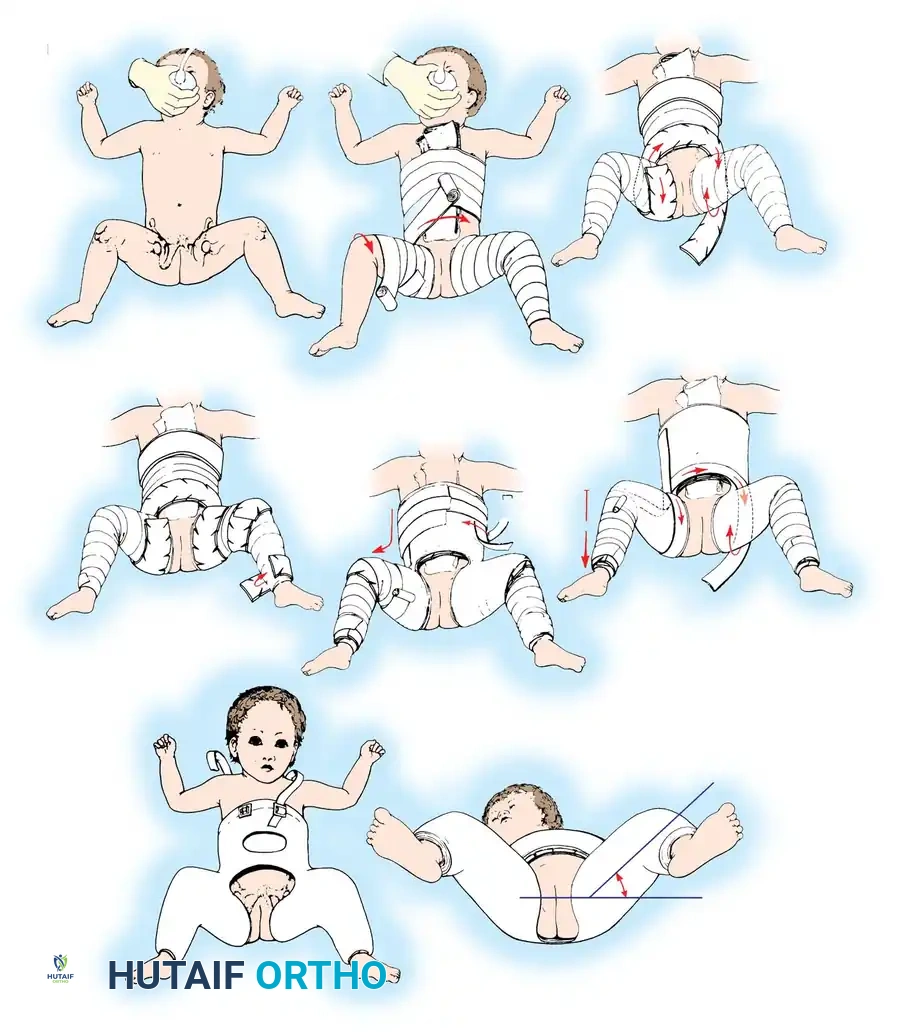

Treatment is directed at stabilizing the reducible hip (positive Ortolani) or reducing the subluxated hip. The Pavlik Harness is the gold standard.

Biomechanics of the Pavlik Harness:

The harness functions as a dynamic flexion-abduction orthosis.

* Anterior straps are adjusted to maintain hip flexion at 100 to 110 degrees. This redirects the femoral head toward the triradiate cartilage.

* Posterior straps prevent adduction but must not force abduction. Forced abduction is the primary cause of iatrogenic avascular necrosis (AVN).

Pitfall: The Pavlik harness is contraindicated in teratologic dislocations (e.g., arthrogryposis, spina bifida) and in infants with severe soft-tissue contractures. Failure to achieve reduction within 3 to 4 weeks is an indication to abandon the harness to prevent "Pavlik harness disease" (posterior acetabular wear).

4. Spica Casting: The hip is immobilized in the "human position"—90 to 100 degrees of flexion and 40 to 50 degrees of abduction. Extreme "frog-leg" positions must be avoided to prevent vascular compromise to the femoral head.

Immobilization:

Following open reduction and osteotomy, patients are placed in a 1.5 spica cast for 6 to 8 weeks. Upon cast removal, an abduction orthosis may be utilized at night to maintain the reduction while allowing daytime mobilization and physical therapy.